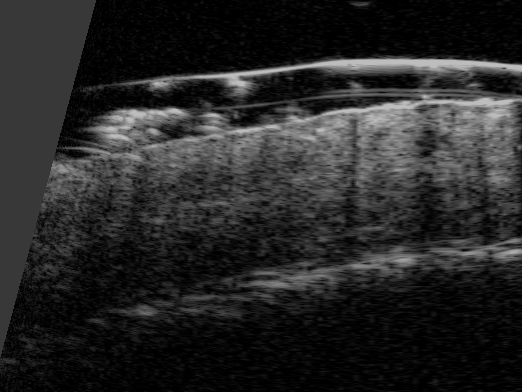

Badanie trychoskopowe,

pozwala na szczegółową ocenę stanu mieszków włosowych, łodyg włosów oraz skóry głowy. W przypadku pacjenta, lat 42, trichoskopia wykazała cechy charakterystyczne dla łysienia androgenowego, takie jak miniaturyzacja mieszków włosowych – proces, w którym mieszki stają się mniejsze i produkują cieńsze, słabsze włosy. Ponadto, badanie ujawniło oznaki reaktywności skóry, w tym nadwrażliwość, rumień oraz stan zapalny. Dzięki temu precyzyjnemu badaniu możliwe było dobranie optymalnej terapii, która nie tylko uspokoiła podrażnioną skórę, ale również stymulowała mieszki włosowe do wzrostu, co pozwoliło na zredukowanie przerzedzenia włosów i poprawę ich struktury.